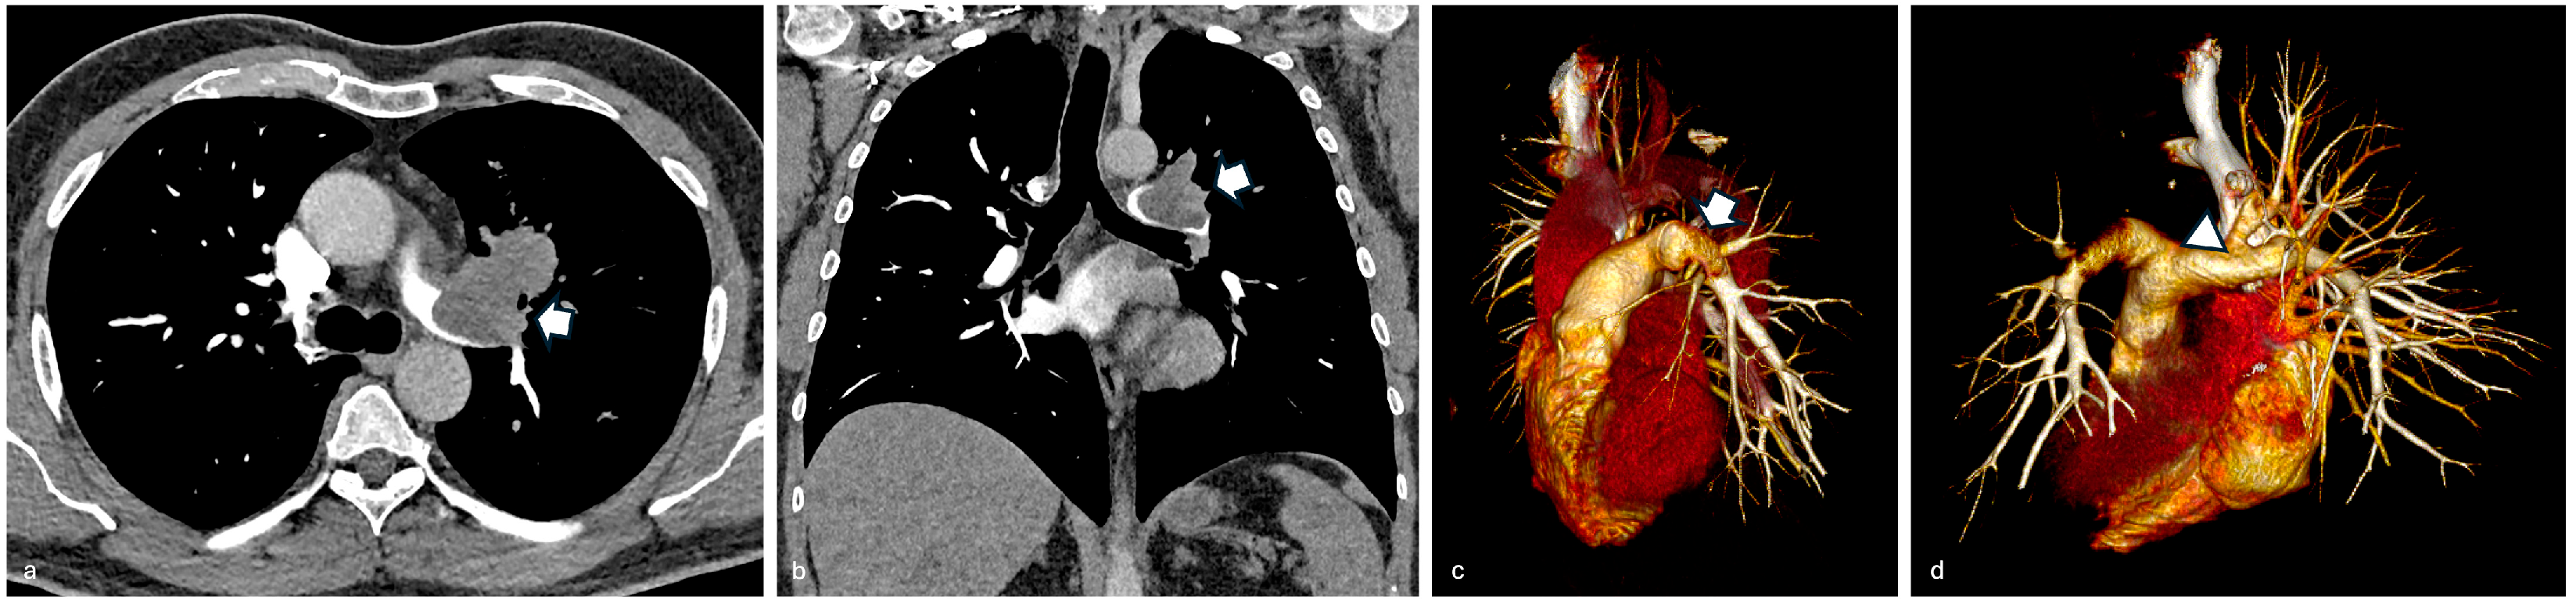

3.2. Case 2